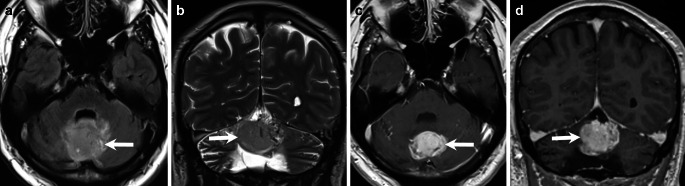

Abstract Image